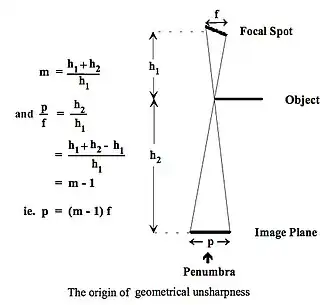

- The physical characteristics of the human body allow radiographs to be recorded at diagnostic X-ray energies and many anatomical structures to be examined. The spatial resolution of such images is found to be highly dependent on the size of the source of X-rays. We have already seen that X-rays can be generated by a tungsten anode, for instance. What we haven’t considered is the size of this source.

- It is found that the smaller this source, the better is the spatial resolution in the recorded radiograph. The reason can be appreciated from Figure 3.11, where it is seen that a focal spot of finite size, f, on the anode target of the X-ray tube (XRT) is used to expose the edge of a opaque object. The image of the edge is seen to be spread out into a penumbra, p, of dimensions depending on the ratio of the distance from the X-ray source to the image (the SID) and the distance from the X-ray source to the object. This ratio is called the Geometric Magnification, m. It is equivalent, on the basis of considering the geometry of this arrangement, to the image size divided by the object size.

- An assumption in deriving the mathematical relationships in the diagram is that the focal spot, f, is indeed parallel with the image plane. This is generally not the case and for technical reasons it is angled, as we will saw earlier.

- Since the size of the penumbra, p, is nevertheless greater than the focal spot size to an extent dependent on the magnification, it can be reduced by any or all of the following:

- reducing the focal spot size, f;

- increasing the source-to-object distance, h1;

- decreasing the object-to-image distance, h2.

- The first option for reducing the focal spot size is limited by the properties of the XRT anode and is generally about 0.5 to 1 mm depending on the application. Its even smaller in Mammography where fine focal spots of 0.1-0.3 mm are common because of the requirement to image microcalcifications.

- The second option gives rise to source-to-image distances (SID) of up to one meter or more being used in diagnostic radiography. The final option is generally applied by placing the part of the body being irradiated as close to the image receptor as possible. However, unity magnification is never achieved because of the finite thickness of the cover of the cassette containing the image receptor and, more importantly, because of the finite thickness of the body part. The posterior surface of the part will receive the smallest magnification, while the anterior surface will be magnified to a greater extent. Intermediate structures will be magnified to an intermediate extent depending on their distance from the image receptor. Additionally, images of these intermediate structures, e.g. bones, can be displaced relative to each other, which can lead to problems in determining their exact anatomical size, shape and location.